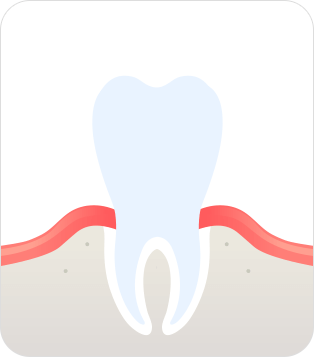

건강한 상태

치아 주위의 잇몸이 핑크색을 띄며,

잇몸에서 피가 나지 않음